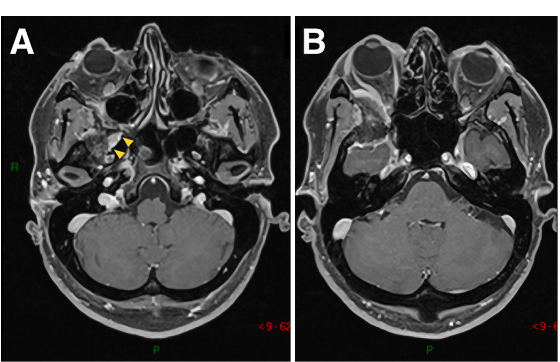

图1A-D:术前MR显示蝶眶区脑膜瘤占位,增强病灶,浸润延伸至蝶腭窝(黄色箭头)。

术中操作:Froelich教授经翼点入路开颅,剥离海绵窦侧壁后,行硬膜外前床突切除术。切除硬脑膜内肿瘤及侵袭硬脑膜及眶周的肿瘤。使用颅包膜补片对硬脑膜缺损进行水密封闭后,剥去圆孔(FR),暴露翼腭窝(PPF)。肿瘤沿V2神经鞘播散生长,磨除上颌窦(MaxS)后,打开蝶窦(SphS)。

术后组织病理学:I级脑膜上皮型脑膜瘤。

术后临床情况:眼球突出症状立即好转,术后恢复好,病程平稳。术后V2神经功能包括角膜感觉正常,无干眼、流泪异常等症状,按期拆线出院。

▼术后影像复查:证实肿瘤被完全切除。E-H:术后轴位MR图像显示肿瘤完全切除。